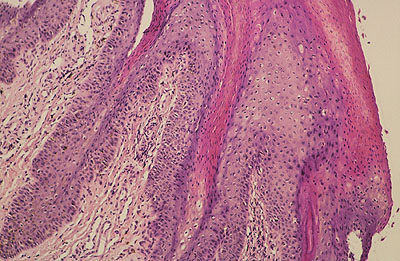

Photo 2 (Hémalun Eosine X 40) : au faible grossissement, l’épiderme revêt un aspect bleu-blanc-rouge,

bleu pour hyperplasie des couches basales, blanc pour vacuolisation des acanthocytes sous-cornés et

rouge pour parakératose de la couche cornée. Le derme est faiblement à modérément inflammatoire.

Légendes de la Photo 2 :

- Flèche bleue : hyperplasie des couches basales

- Flèche blanche : vacuolisation des acanthocytes sous-cornés

- Flèche rouge : pour parakératose de la couche cornée

- Étoile rouge : Le derme est faiblement à modérément inflammatoire